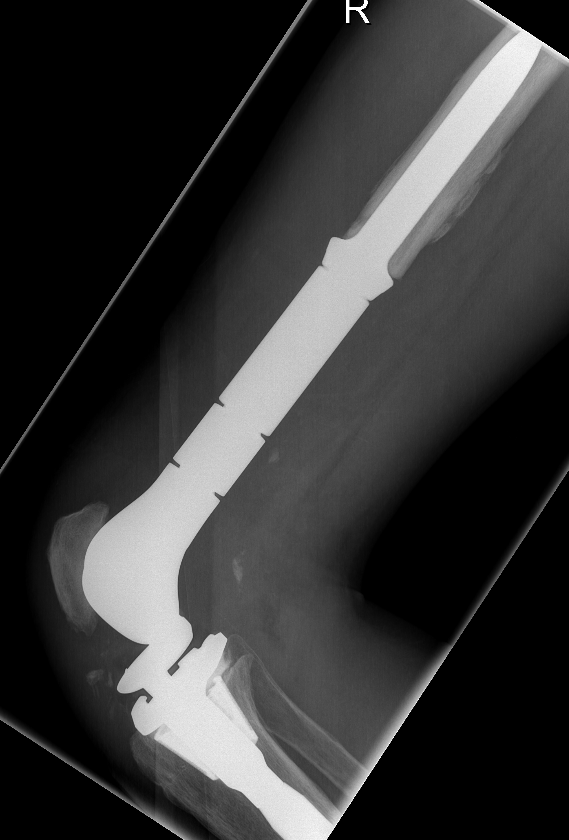

Post distal femoral osteosarcoma resection